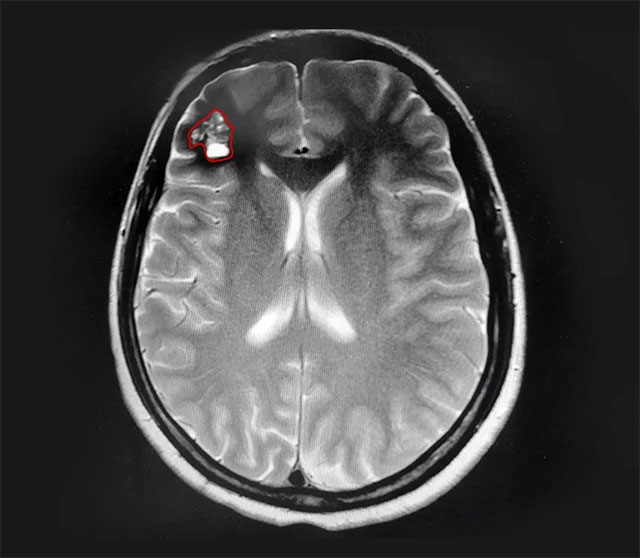

▲ 患者右側(cè)額葉可見(jiàn)桑葚樣團(tuán)塊

患者的頭暈癥狀持續(xù)數(shù)年且于近期加重,已影響正常生活,結(jié)合病情進(jìn)展和影像學(xué)資料,沈建康教授和神經(jīng)外科6A病區(qū)侯增欣主任等專(zhuān)家開(kāi)展了嚴(yán)謹(jǐn)?shù)脑u(píng)估和討論,認(rèn)為患者具有手術(shù)指征。在告知手術(shù)風(fēng)險(xiǎn)并取得家屬同意后,由沈建康教授主刀,為錢(qián)女士行血管瘤切除手術(shù)。

在電生理監(jiān)測(cè)的保駕護(hù)航下,沈教授利用神經(jīng)導(dǎo)航技術(shù)成功定位病變部位,并采用經(jīng)腦溝入路技術(shù),減少患者腦部皮質(zhì)損傷直達(dá)病變部位。顯微鏡下可見(jiàn),病變部位呈褐色桑葚狀,周?chē)X組織黃染。“這是由于海綿狀血管瘤自發(fā)性反復(fù)小量出血,造成的鐵血黃素沉著。”沈教授解釋道。借助先進(jìn)的神經(jīng)導(dǎo)航技術(shù),在蔡司顯微鏡(雙熒光)下,沈教授順利切除血管瘤,并剔除黃染組織,術(shù)中無(wú)明顯副損傷。